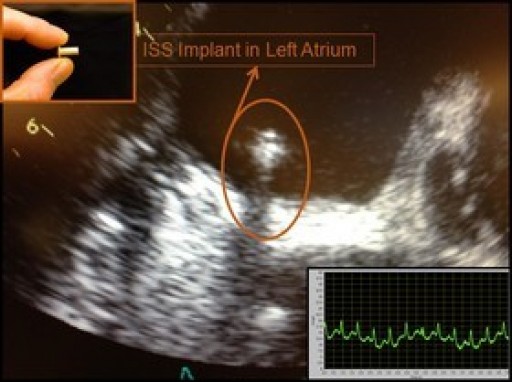

Method for Adding Intelligence to LVADs: Exhibition at ASAIO 61st Annual Conference

ISS will exhibit a practical way to add intelligence to LVAD's at the ASAIO 61st Annual Conference (June 24-27, 2015).

Intelligent Left-Heart Implantable Hemodynamic Monitor: Oral Presentation at the ESC Heart Failure Conference

Results of intelligent, wireless, left-heart, implantable, hemodynamic monitor will be presented at the Heart Failure Conference in Sevilla, Spain (May 23-26, 2015).